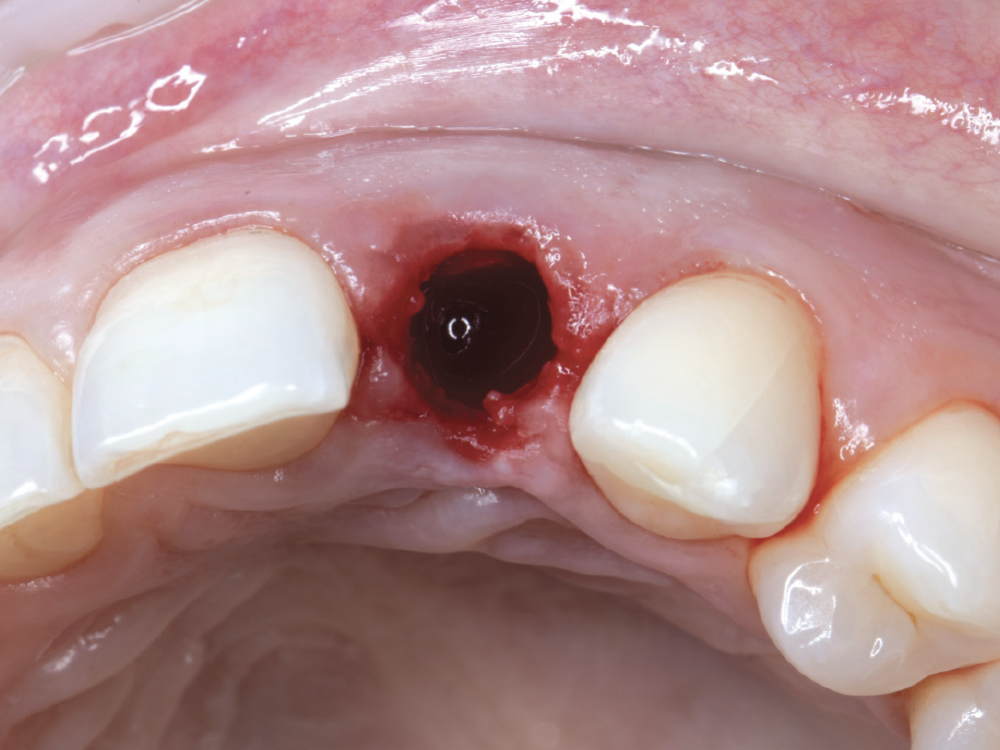

The tooth was removed as atraumatically as possible. Due to its ankylosed condition, portions of the root needed to be removed with a surgical carbide bur.

Figure 9: The tooth was removed as atraumatically as possible. Due to its ankylosed condition, portions of the root needed to be removed with a surgical carbide bur.

After extracting the tooth, the surgical guide was tried in. Once it was confirmed that the guide was fully seated, the osteotomy was performed.

Figure 10: After extracting the tooth, the surgical guide was tried in. Once it was confirmed that the guide was fully seated, the osteotomy was performed.